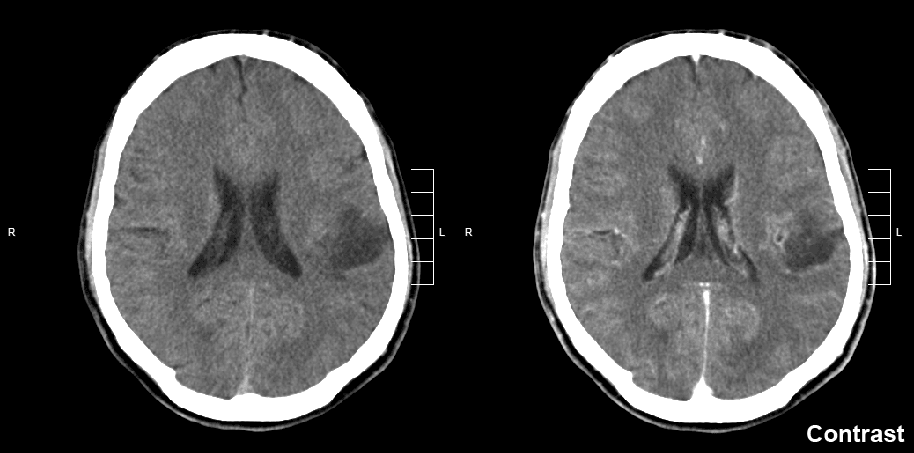

A glioma is a type of tumor that starts in the glial cells of the brain or the spine. Gliomas comprise about 30 percent of all brain tumors and central nervous system tumours, and 80 percent of all malignant brain tumours. Symptoms of gliomas depend on which part of the central nervous system is affected. A brain glioma can cause headaches, vomiting, seizures, and cranial nerve disorders as a result of increased intracranial pressure. A glioma of the optic nerve can cause vision loss. Spinal cord gliomas can cause pain, weakness, or numbness in the extremities. Gliomas do not usually metastasize by the bloodstream, but they can spread via the cerebrospinal fluid and cause "drop metastases" to the spinal cord. Complex visual hallucinations have been described as a symptom of low-grade glioma. A child who has a subacute disorder of the central nervous system that produces cranial nerve abnormalities (especially of cranial nerve VII and the lower bulbar nerves), long-tract signs, unsteady gait secondary to spasticity, and some behavioral changes is most likely to have a pontine glioma. The exact causes of gliomas are not known. Hereditary disorders such as neurofibromatoses (type 1 and type 2) and tuberous sclerosis complex are known to predispose to their development. Different oncogenes can cooperate in the development of gliomas. Some studies of diet and vitamin supplementation appear to point out that dietary N-nitroso compounds may affect the risk of both childhood and adult brain tumors. Researchers have observed in some studies that brain tumor patients (or their mothers) have generally consumed more cured foods (also known as Curing) than control groups. Recently, Drs. Lee, Wrensch and others found that adults with glioma were more likely to consume diets high in cured foods and low in vitamin C-rich fruits and vegetables, and to consume diets high in nitrites and low in vitamin C. The effect was more pronounced in men than women.